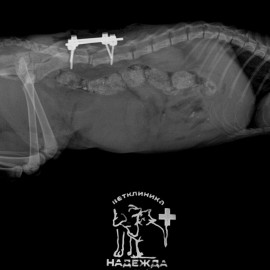

У кошечки была травма, покусана собакой в поясничной области позвоночника. При обращении в клинику отмечались жалобы на слабость тазовых конечностей, шаткая походка. После проведения рентгенологического исследования поставлен диагноз - перелом позвоночника на уровне L6-L7. Была проведена операция - остеосинтез позвоночника L6, спондилодез позвоночника на уровне L5-L7.

Снимок 2 после операции.